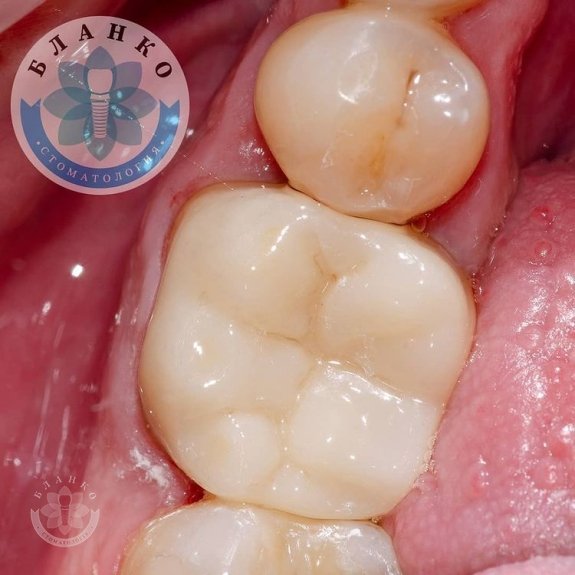

- знято відбитки та виготовлено високоміцну, гіпоалергенну та високоестетичну коронку з діоксиду цирконію.